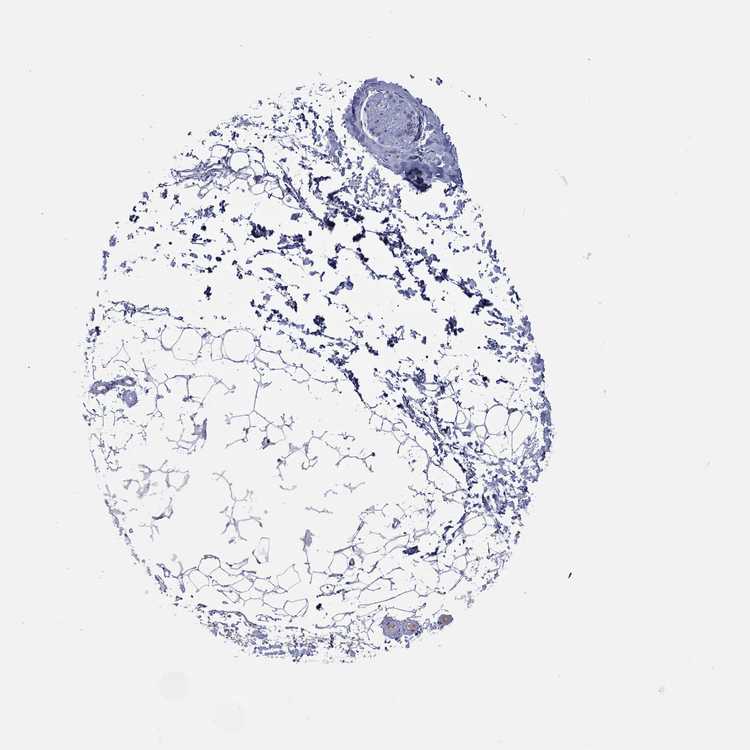

SOFT TISSUE 1 - Antibody stainingi

Antibody staining in the annotated cell types in the current human tissue is reported as not detected, low, medium, or high, based on conventional immunohistochemistry profiling in selected tissues. This score is based on the combination of the staining intensity and fraction of stained cells.

Each image is clickable and will lead to virtual microscopy that enables deeper exploration of all samples and also displays staining intensity scores, fraction scores and subcellular localization as well as patient and tissue information for each sample.

Antibody HPA015103

Chondrocytes Not detected

Fibroblasts Not detected

Peripheral nerve Not detected